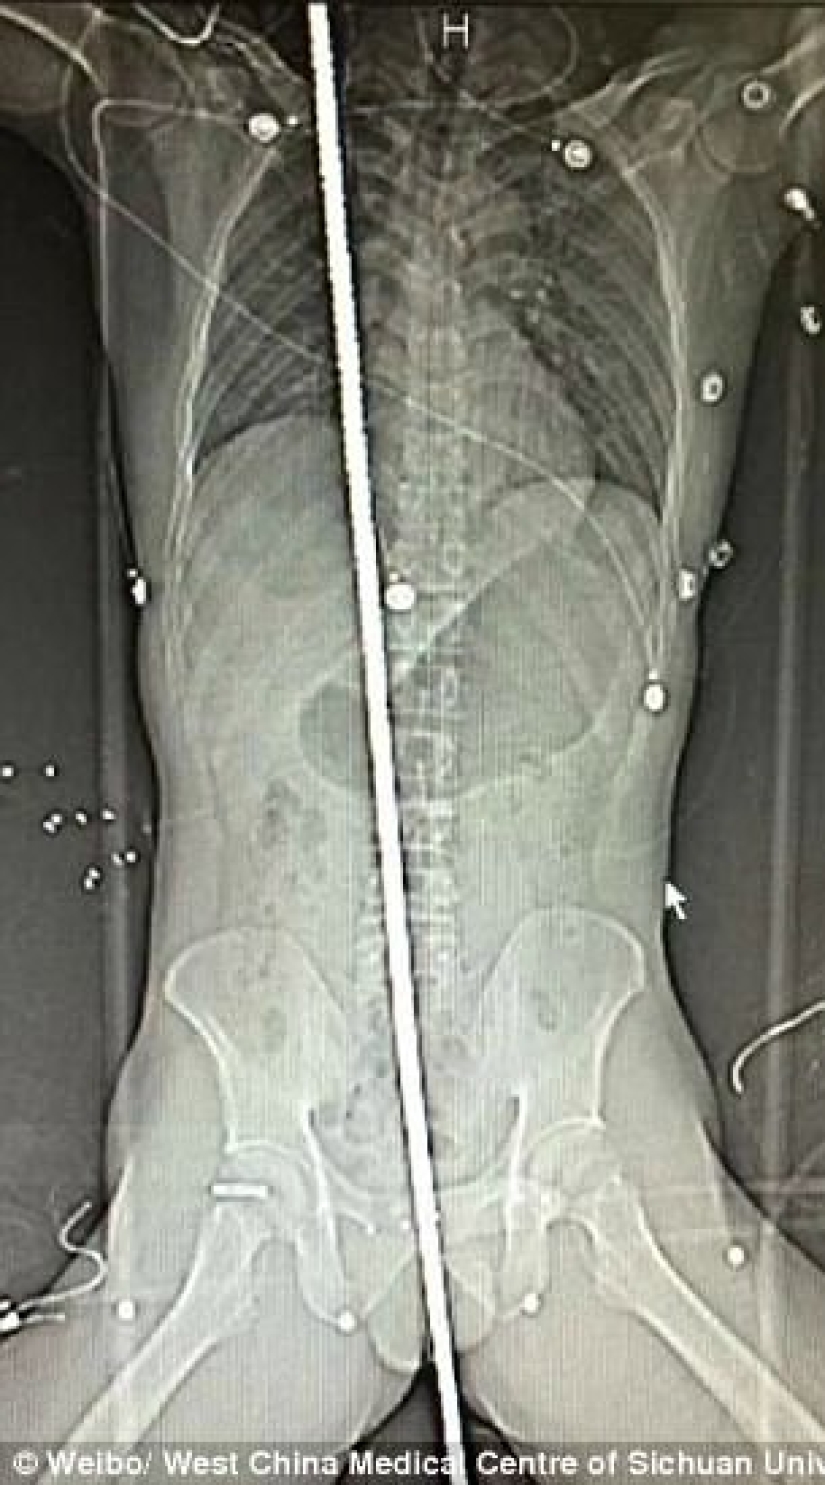

El 18 de septiembre, un hombre de 37 años fue alcanzado por un rayo en un sitio de construcción en Chengdu, suroeste de China. Se cayó y aterrizó justo en la barra de refuerzo que sobresalía. Una viga de metal de dos metros atravesó todo el cuerpo. La víctima fue hospitalizada de urgencia.

La radiografía mostró que la varilla perforó el diafragma y atravesó el lado derecho del saco pericárdico.

Los médicos realizaron una operación de siete horas, extrajeron el tejido dañado de los pulmones y el hígado y luego extrajeron con éxito la varilla de metal.